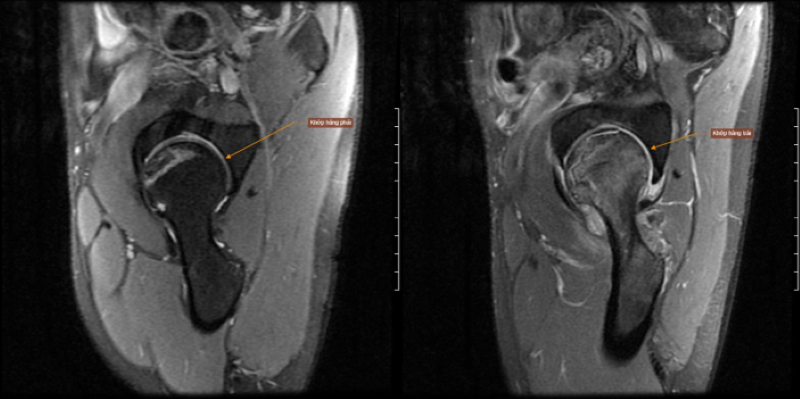

Tại đây, bác được các bác sĩ tiến hành thăm khám toàn diện, thực hiện chụp MRI khớp háng hai bên và xác định tình trạng hoại tử vô khuẩn chỏm cầu xương đùi (bên trái độ III, bên phải độ II theo phân loại ARCO) kết hợp viêm cơ khép háng trái và viêm cơ khép - chính là nguyên nhân gây đau.

Hình ảnh hoại tử vô khuẩn chỏm xương đùi hai bên, ưu thế bên trái